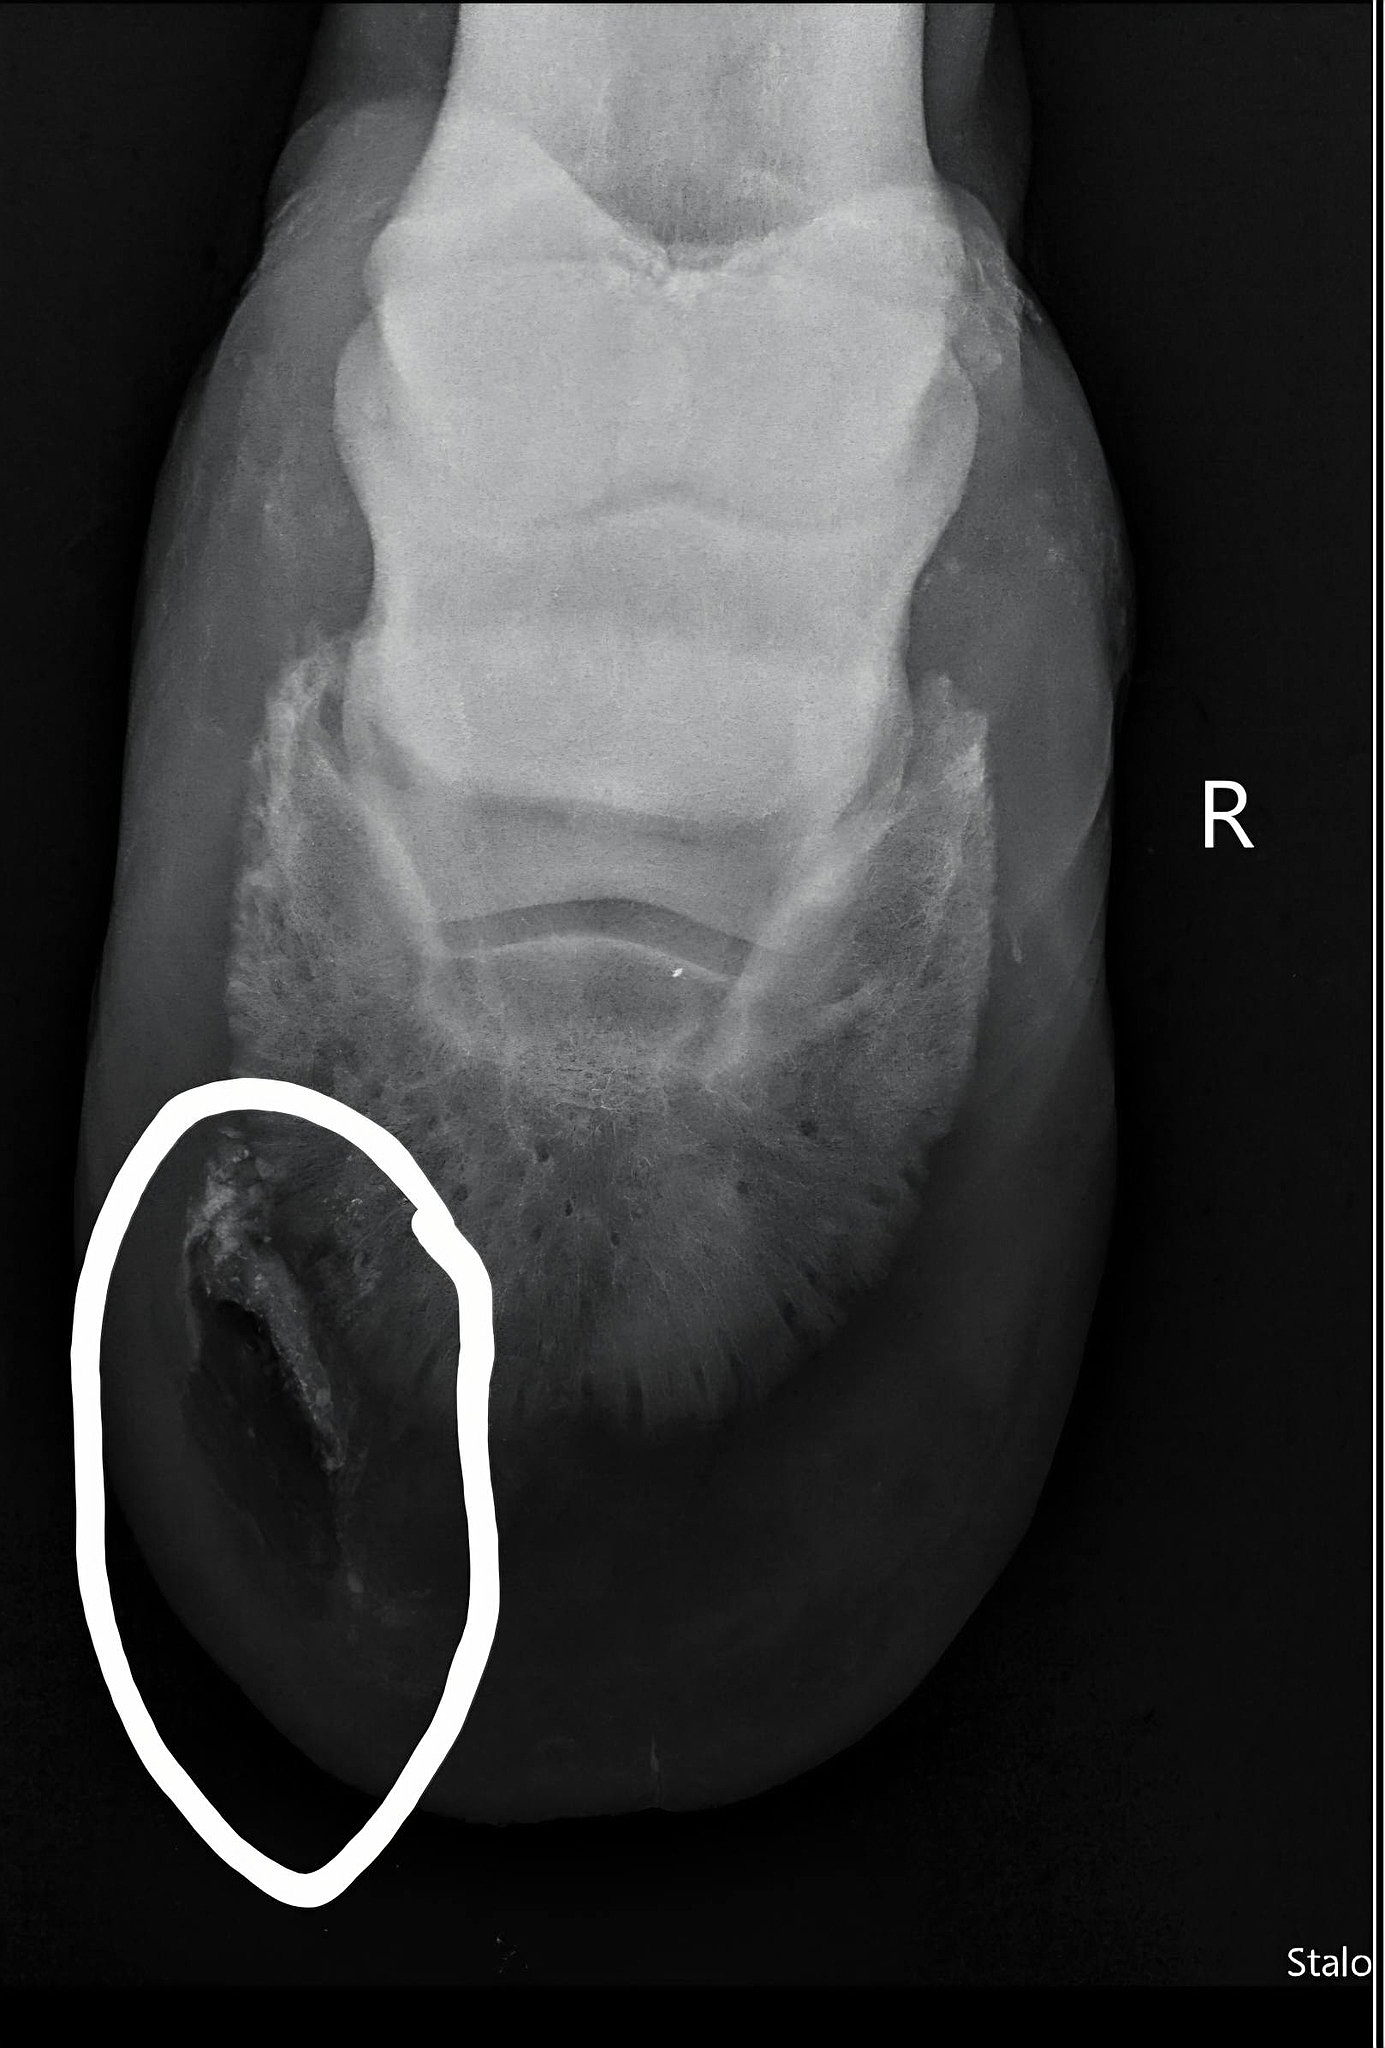

Titan is a 13-year-old Thoroughbred gelding with a heart as big as his stride. A retired racehorse, he came to us as an owner surrender when his former owner was going through a difficult divorce. When he arrived, we quickly discovered he was battling a severe hoof abscess that had eaten away a significant portion of his hoof.

Thanks to immediate veterinary care, X-rays confirmed the infection had not reached his coffin bone — a huge relief. Since then, Titan has been on the mend, receiving careful treatment, farrier work, and lots of love. Every day he grows stronger.